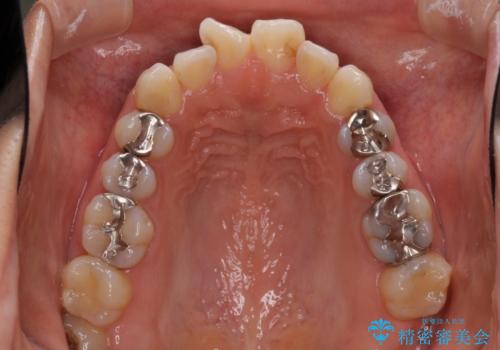

- 上の前歯の捻じれと突出感を気にして来院された患者様です。

目立たない装置を希望とのことで、上顎左右第一小臼歯を抜歯し、インビザラインにて矯正治療を行うこととしました。